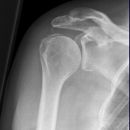

Schulter nach Morrison oder Outlet View

Indikation

v.a. Impingementsyndrom: Beurteilung des Akromions, des AC-Gelenks, evtl. hilfreich zur Diagnostik von Luxationen

Beurteilungskriterien

- Impingementsyndrom (2): Neigungswinkel des Akromions -> Je gebogener bzw. hakenförmiger desto höher ist die Wahrscheinlichkeit. Radiologische Befunde: Zystenbildung im Bereich des Tuberculum majus? Subchondrale Sklerosierung am Tuberculum majus oder subacromiale Osteophytenbildung? Verkalkungen im Verlauf der Supraspinatussehne?

- subacrominalen Raumes: normalerweise 1 - 1,5 cm, < 10 mm -> wahrscheinlich, < 6 mm -> sicher pathologisch